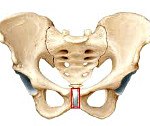

Систематизация форм симфизита, связанного с беременностью и родами, учитывает величину расхождения костей лонного сочленения. Выбор критерия классификации обусловлен прямой взаимосвязью клинической картины расстройства с расстоянием между костями, которые соединяет лобковый симфиз. На основании этого параметра акушеры-гинекологи различают 3 степени тяжести заболевания:

• I степень. Кости лонного сочленения расходятся на 0,5 - 0,9.

• II степень. Величина расхождения в симфизе составляет 1,0 - 1,9.

• III степень. Расстояние между лобковыми костями превышает 2,0.